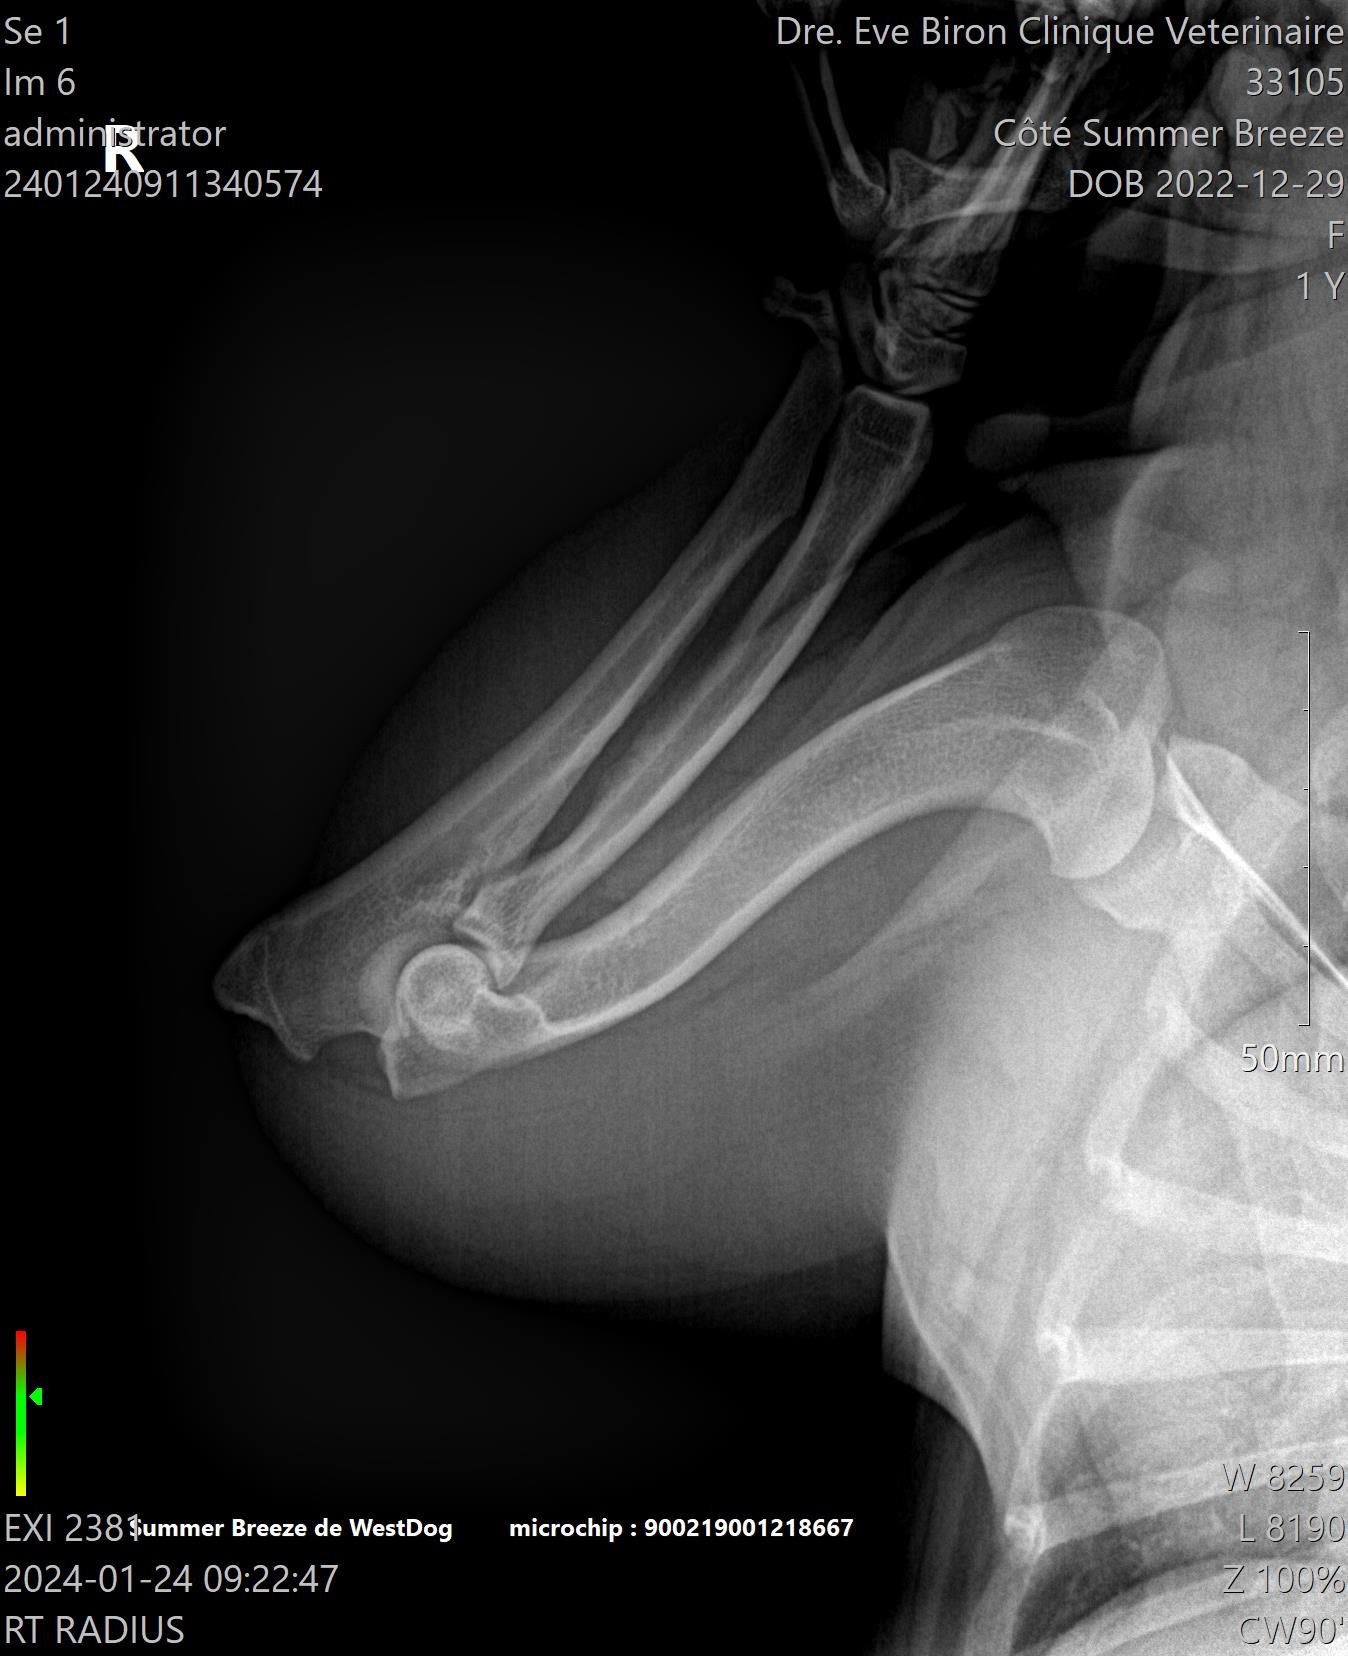

L’OFA recommande de faire des tests de biomécanique du chien: Dysplasie de la hanche, Luxation des rotules, Examen oculaire, évaluation cardiaque, Coude, Thyroïdite, et Trachée.

Tous ces tests doivent être fait par des vétérinaires et certains laboratoires accrédités. La vérification de l’enregistrement original du chien AKC et de l’identification par micropuce ou tatou est obligatoire pour que le vétérinaire puisse signer et envoyer les radiographies de façon électronique, de la clinique vétérinaire à L’OFA et ainsi éviter les fraudes.

L'OFA est un organisme à but non lucratif situé aux États-Unis qui permet de publier les résultats des tests fait par les vétérinaires et les laboratoires accrédités. 3 vétérinaires indépendants spécialisés, évaluent les radiographies et leurs donnent des “quotes”. C’est une excellente façon de prouver qu’un éleveur a le souci de dépister des problèmes potentiels sur les animaux qu’il prévoit reproduire, et de montrer au public les résultats des épreuves complétées. Comme la majorité des gens ne sont pas spécialisés en lecture de radiographies, les notes données par L’OFA sont impartiales et permettent d’avoir une vraie vue d’ensemble.

Pour la méthode traditionnelle, celle de l’OFA (Orthopedic Foundation for Animals), une seule radiographie est prise. Avec la méthode PennHIP, ce sont trois prises de vues qui sont réalisées. Elles permettent au vétérinaire de détecter la présence d’arthrose dans l’articulation et de calculer le degré de relâchement (s’il y en a un). Le PennHIP peut être effectué à partir de l’âge de 16 semaines, ce qui en fait une méthode de dépistage précoce. La dysplasie de la hanche est une maladie génétique qui affecte les chiots dès leur plus jeune âge.